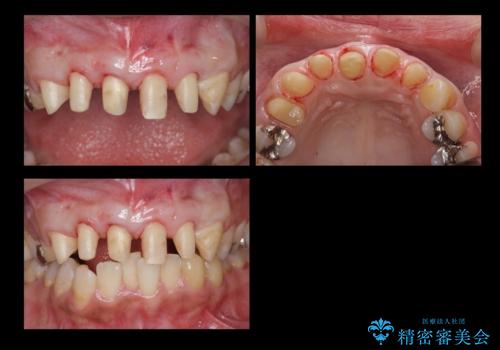

前歯の虫歯 つぎはぎの歯をセラミックに

- 前歯の被せもののやり直しを希望して来院。

隣の歯もつぎはぎでプラスチックが劣化していたため、虫歯を取りセラミックでかぶせました。

保険治療の前歯の被せものの縁(マージン)が歯茎の中まで及んでいたため、歯周外科手術を行い、マージンが歯肉縁下深くならないように設定しました。